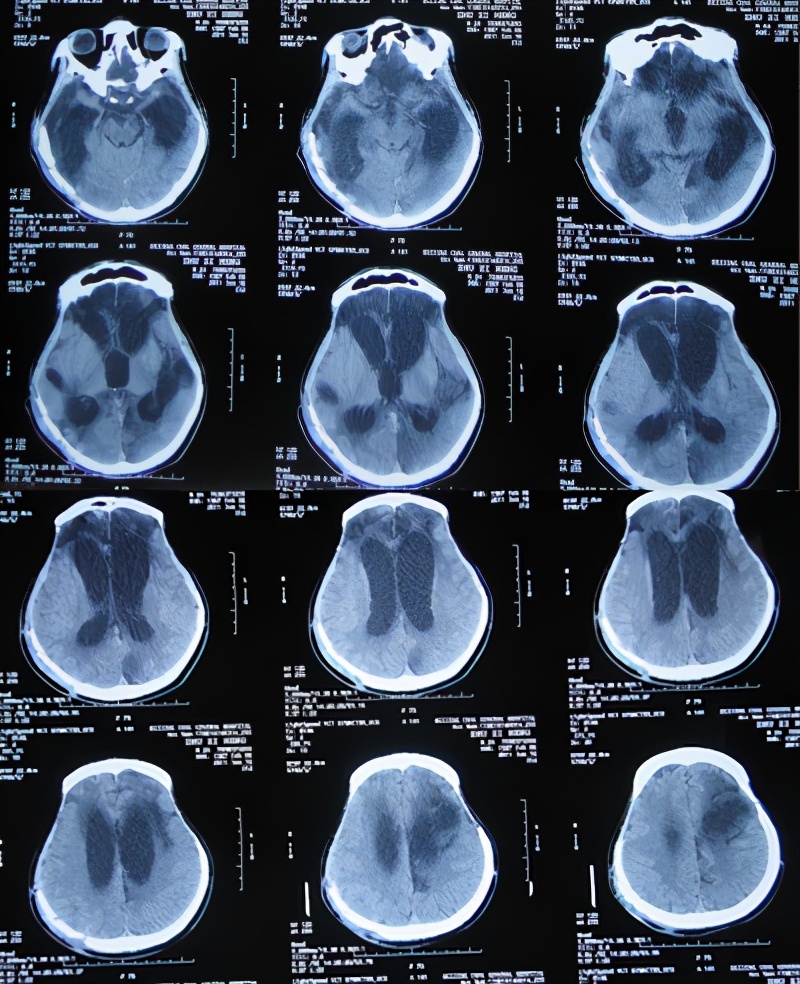

患者于2011年1月14日晚11点,意外发生车祸当即昏迷,120救护车将其送往第1家的安徽省合肥市的某三甲医院,查头颅CT:重度颅脑损伤,脑出血( 图-1 )。

图-1: 2011年1月15日头颅CT

当天急诊去骨瓣减压术;术后当天查头颅CT示双侧去骨瓣减压术后状态( 图-2 )。

图-2: 2011年1月15日术后头颅CT